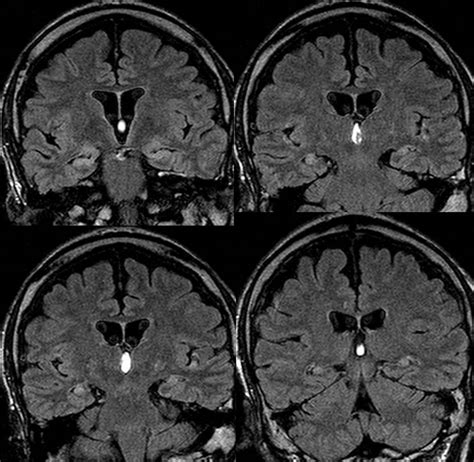

3. MRI (Magnetic Resonance Imaging) : MRIs use powerful magnets and radio waves to create detailed images of the body’s internal structures. They are especially good at imaging soft tissues, making them useful for looking at the brain, spinal cord, and other areas where tumors might be present. In the context of bilateral MTS radiology , MRI can provide crucial information about the spread of cancer to the central nervous system or other sensitive areas.